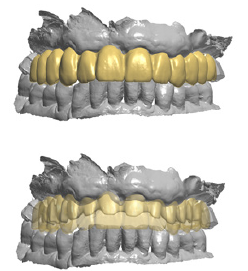

In the resulting post-surgical intermaxillary space, a fixed full-arch temporary prosthesis was digitally designed and manufactured in a complete digital workflow (CAD/CAM) with the occlusal plane parallel to the Camper’s plane and the bipupillary plane, it was then screwed on the implants (Figures 7-12). The definitive prosthesis will be fabricated once the implants are integrated and both hard and soft tissue are healed and stable.

Figure 7: Frontal and sagittal view of the design of the temporary maxillary full-arch prosthesis.

As seen in the previous case, in the resulting post-surgical intermaxillary space, a fixed full-arch temporary prosthesis was digitally designed and manufactured in a complete digital workflow (CAD/CAM) with the occlusal plane parallel to the Camper’s plane and the bipupillary plane, it was then screwed on the implants (Figures 15-22). The definitive prosthesis will be fabricated once the implants are integrated and both hard and soft tissue are healed and stable.

Figure 15: Maxillo-mandibular relationship in patient’s habitual occlusion in maximum intercuspation obtained matching the pre-surgical and post-surgical digital scans.

Figure 16: Design of the temporary maxillary full-arch prosthesis. Fontal view.

Figure 17: Design of the temporary maxillary full-arch prosthesis. Occlusal view.